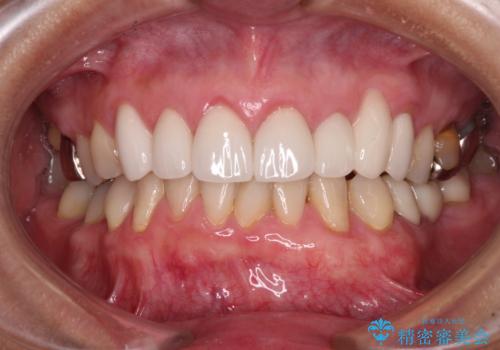

歯肉移植による根面被覆の結果、しみる症状は一切なくなりました。

歯肉の厚みが増したため、歯肉退縮のリスクが軽減されましたが、定期的に症状が再発していない確認していくことになります。